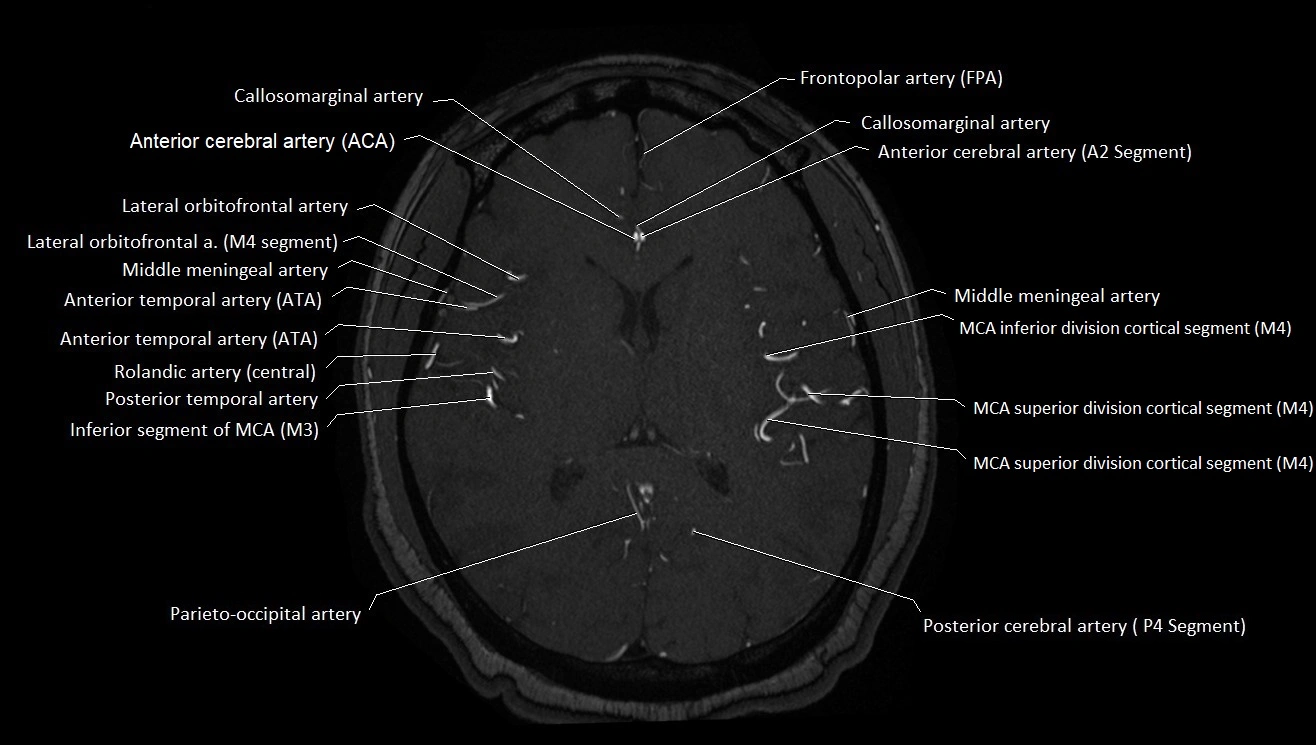

MRA (Magnetic Resonance Angiography):

• Flow-related enhancement makes the AChA appear as a bright, linear vascular signal against suppressed background

• High sensitivity for origin and proximal course; distal branches may be too small to resolve

• Detects stenosis, occlusion, aneurysm, AVM feeders

MRI images

image